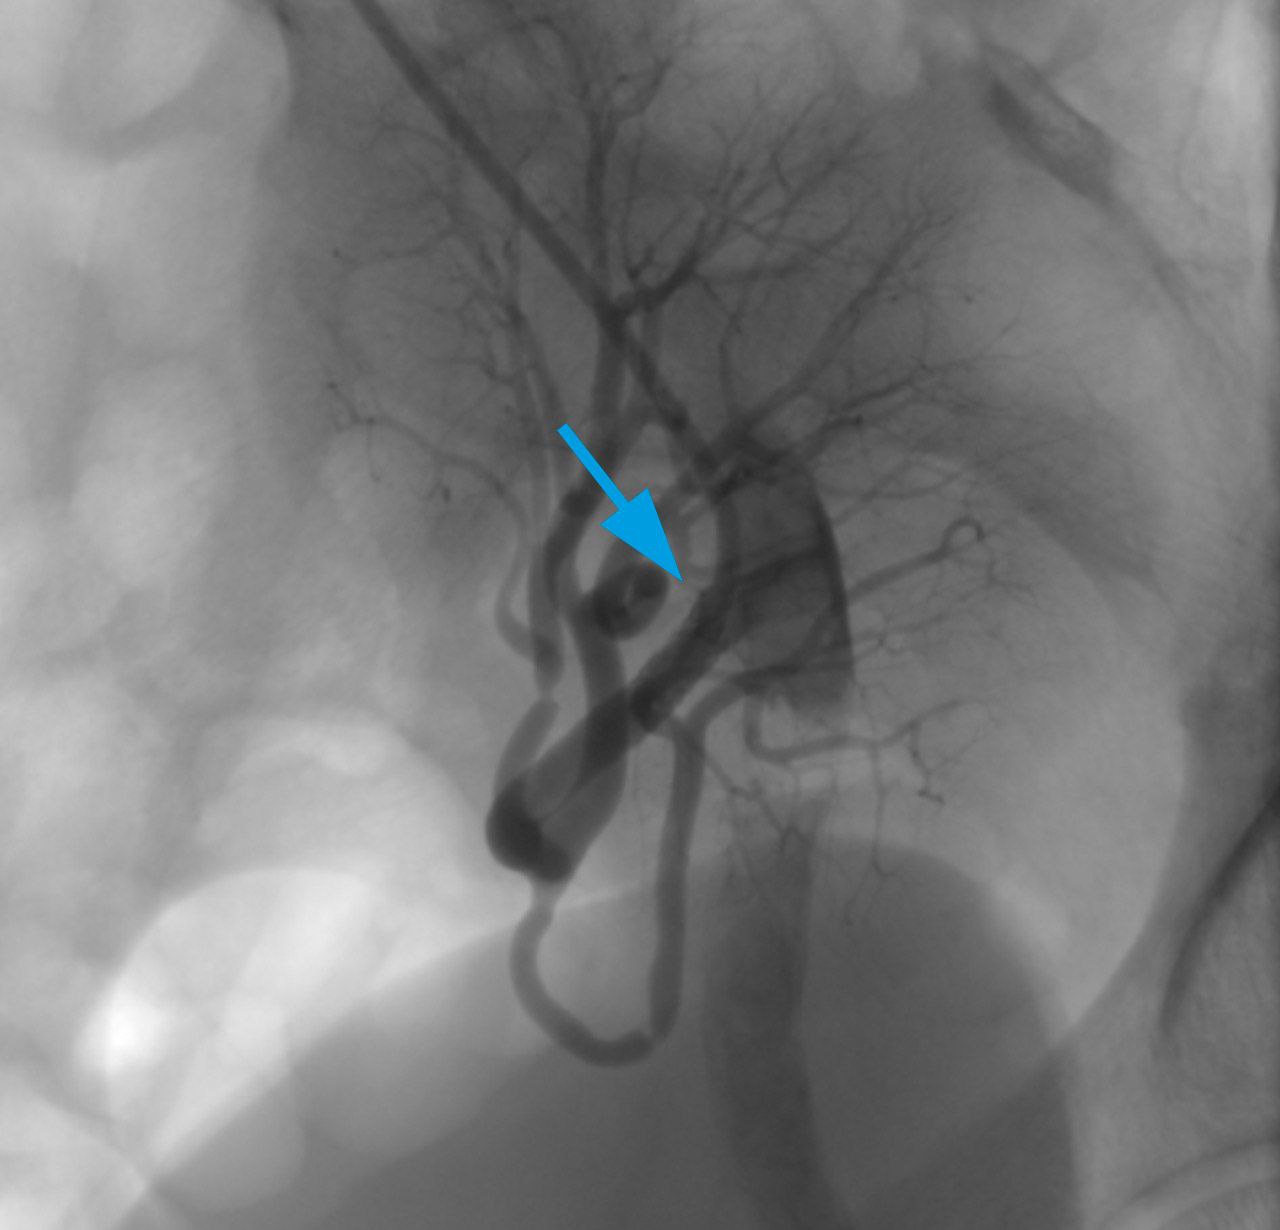

На финальных анигограммах был зафиксирован успешный результат стентирования артерии почечного трансплантата (рис. 3).